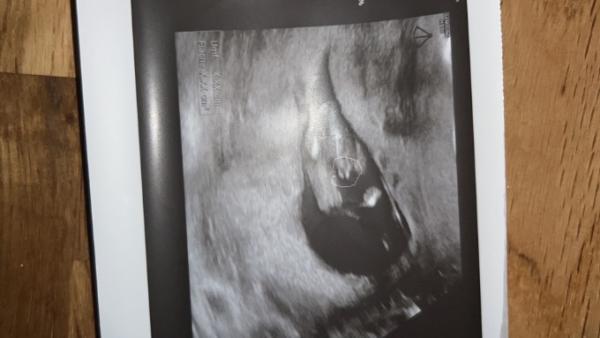

Hallo :) Ich weiß nicht in welche Kategorie dies gehört, da ich mich eben erst angemeldet habe. Ich bin in der 15. SSW und wollte mal fragen ob ihr auf dem Bild erkennen könnt, ob es ein Junge oder ein Mädchen wird :) mein Arzt sagt : zu 95 % ein Junge. Aber so früh, sehen die Genitalien sich ja noch sehr ähnlich und auch ein Arzt kann sich mal vertun. :p was meint ihr ?

Ich würde auch sagen, dass es ein Junge wird ![]()